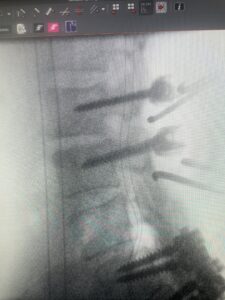

This 61-year-old female with a history of severe osteoporosis and a prior history of a laminectomy from l2-S1 with an L5-S1 instrumented fusion, presents with progressive low back pain and right lower extremity radiculopathy. MRI revealed a grade 1 L2-3 spondylolisthesis with severe stenosis mainly from severe right L2-3 facet joint hypertrophy which was compressing the right L3 descending nerve root. (Fig. 1). She had failed conservative management consisting of physical therapy and pain management with epidurals. She underwent an L1-3 revision laminectomy where we had to dissect a plane underneath the inferior aspect of the L2 lamina. We performed an instrumented fusion at L2-3 with special hydroxyapatite-coated screws to improve fixation to surrounding bone given here severe osteoporosis (Fig. 2) This worked out well and the patient had an uneventful recovery with relief of her leg pain.

Fig: 2a: AP and lateral intraoperative fluoroscopic images demonstrating good placement of L2-3 pedicle screws